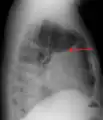

A pleural effusion appears as an area of whiteness on a standard posteroanterior chest X-ray.[14] Normally, the space between the visceral pleura and the parietal pleura cannot be seen. A pleural effusion infiltrates the space between these layers. Because the pleural effusion has a density similar to water, it can be seen on radiographs. Since the effusion has greater density than the rest of the lung, it gravitates towards the lower portions of the pleural cavity. The pleural effusion behaves according to basic fluid dynamics, conforming to the shape of pleural space, which is determined by the lung and chest wall. If the pleural space contains both air and fluid, then an air-fluid level that is horizontal will be present, instead of conforming to the lung space.[15] Chest radiographs in the lateral decubitus position (with the patient lying on the side of the pleural effusion) are more sensitive and can detect as little as 50 mL of fluid. Between 250 and 600mL of fluid must be present before upright chest X-rays can detect a pleural effusion (e.g., blunted costophrenic angles).[16]

A pleural effusion as seen on lateral upright chest x-ray- Pleural effusion as seen behind the heart.[19]